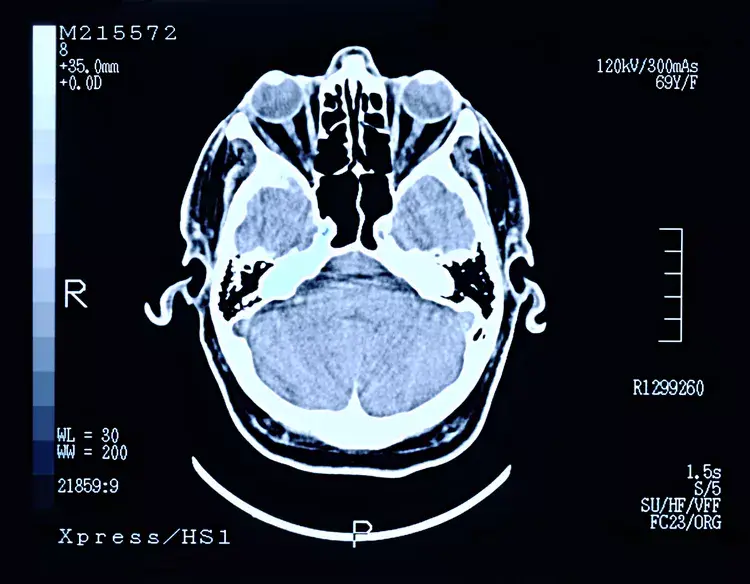

Expert-reviewed radiology reports based on images, enhanced with PrecisionPlus v3™ for clear and confident initial diagnosis.

PrecisionPlus v3™ reports go beyond traditional text-based interpretations. They combine expert MRI analysis with colorized key images, custom medical illustrations, and plain-language summaries, making complex findings easier to understand for physicians, patients, and legal professionals.